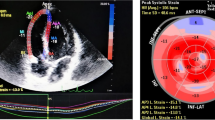

Measurement of right ventricular strain

Strain measurements by two-dimensional speckle-tracking echocardiography method were conducted according to the recommendations of the current echocardiography guideline [16]. All of the images were analysed using 2D AutoStrain software (Qlab, Philips Healthcare, Andover, Massachusetts). Since there was no software to process the right ventricular strain pattern, the software for the left ventricular strain pattern was used. After tracing the RV endocardial border, the region of interest was automatically generated. Global right ventricular free wall strain value was calculated as the mean of the strain values in the 3 segments of the RV free wall.

Echocardiography parameters were given in the Table 2. LVEDD and LVESD, IVS and PW, LVEF and LA diameters were similar between the groups. By using PW, while late diastolic peak velocity (A) was higher in the patient group compared to the healthy group, transmitral early diastolic peak velocity (E) was similar in both groups. While the RV height was significantly higher than the control group, the right ventricular end-diastolic diameter was lower than the control group. Right ventricular end-diastolic and end-systolic area were statistically higher than control group (p < 0.001). The RVFAC was significantly less in the patient group compared to the control group (43.4 ± 7.8 vs. 51.5 ± 6.2; p < 0.001). TAPSE was within normal limits in both groups however, it was lower in the patient group compared to the control group (p 0.006). Pulmonary artery pressure was found to be significantly higher in the patient group compared to the control group (27.9 ± 4.8 mmHg vs 22.2 ± 7.3 mmHg; p < 0.001). While PW and transtricuspid early diastolic (E) were similar in both groups, late diastolic (A) was lesser in control group.Tricuspid valve S, E, A values evaluated by tissue Doppler were similar in both groups. MPI calculated by right ventricular tissue Doppler was significantly higher in the patient group compared to the control group (0.58 ± 0.06 vs. 0.39 ± 0.04; p < 0.001). Right ventricular GLS was measured less than the control group (− 15.7 [(− 12.6)–(− 18.7)] vs. − 18.1 [(− 14.8)–(− 21)]; p 0.011). Right ventricular free wall strain was found to be significantly less in the patient group compared to the control group (− 16 [(− 12.7)–(− 19)] vs − 21.6 [(− 17)–(− 25.3)]; p < 0.001) (Fig. 1).